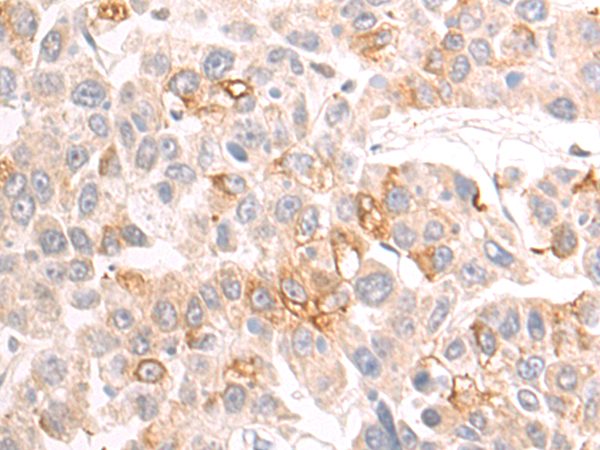

The image is immunohistochemistry of paraffin-embedded Human liver cancer tissue using P03662(STUB1 Antibody) at dilution 1/75. (Original magnification: ×200) |